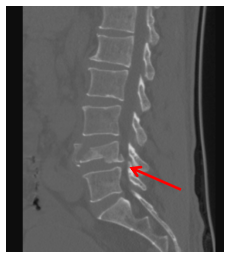

手术详细过程:在C型臂X光机的全程精准透视引导下,宿瑞强主治医师如同一位高超的导航员,在患者背部精准定位。通过六个微小皮肤切口,他避开了重要的肌肉群,沿着预定的安全通道,将六枚空心椎弓根螺钉如“定海神针”般,精准植入骨折椎体上下相邻的健康椎体内。随后,通过皮下隧道置入预弯好的连接棒,利用螺钉的提拉复位力量,宛如用“千斤顶”一般,将被压扁的椎体近乎完全恢复到原有高度,重建了脊柱的正常序列与稳定性。较传统开放手术术中出血大大减少。

(术后X片)